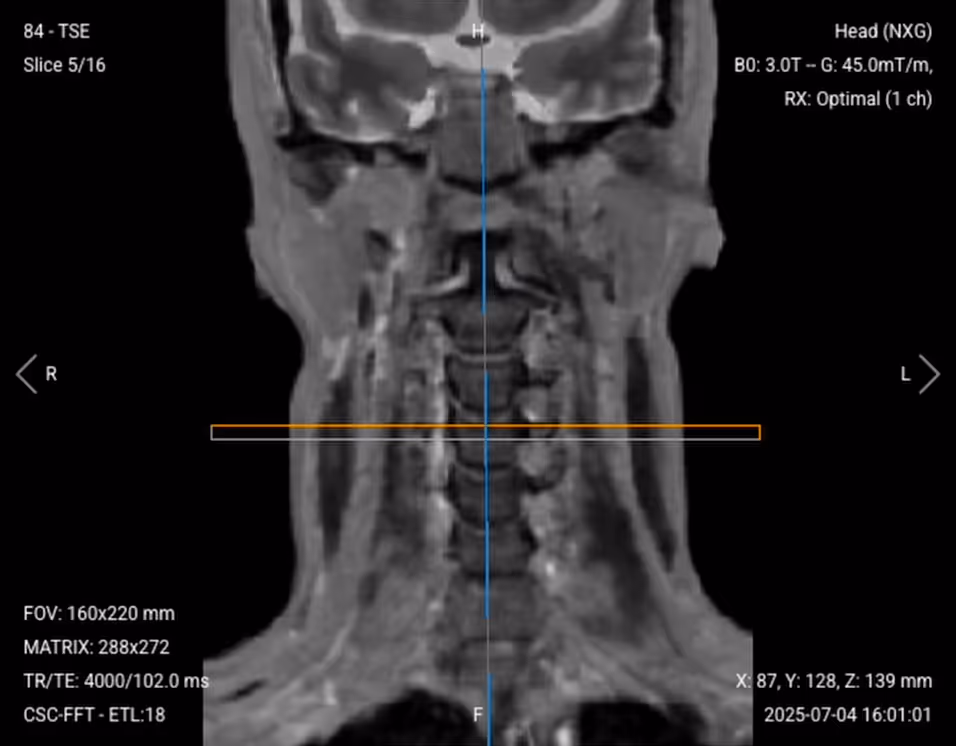

5. Planning Axial T2 TSE

✅ Correct Planning:

Correct planning of axial T2 TSE in 3T

Planning Instructions:

• Use the cervical spine and intervertebral discs as your anatomical references.

• Align the slices as follows:

• Sagittal localizer: Slices should be perpendicular to the cervical spine.

• Coronal localizer: Slices should run parallel to the intervertebral spaces.

• Use appropriate geometry parameters:

• Slice number: Enough to cover all seven cervical discs (C1-C7), typically 20–25 slices.

• Slice thickness: 3 mm, same as other sequences.

• Slice gap: 0.3 mm, maintains consistency.

• Set the fold-over direction (phase encoding) to anterior-posterior (AP) to align with the axial anatomy shape.

• Place a saturation band on the patient's throat to suppress swallowing artifacts without covering the cervical discs.

Axial T2 TSE of the Cervical Spine – Correct Image Example:

Axial T2 TSE of the Cervical Spine – Correct Image Example

Things to Look for in Axial T2:

• Central canal should be patent with bright CSF.

• Disc material should not indent the thecal sac.

• Neural foramina should be symmetric and uncompressed.

• Look for any soft tissue masses or ligamentum flavum hypertrophy.